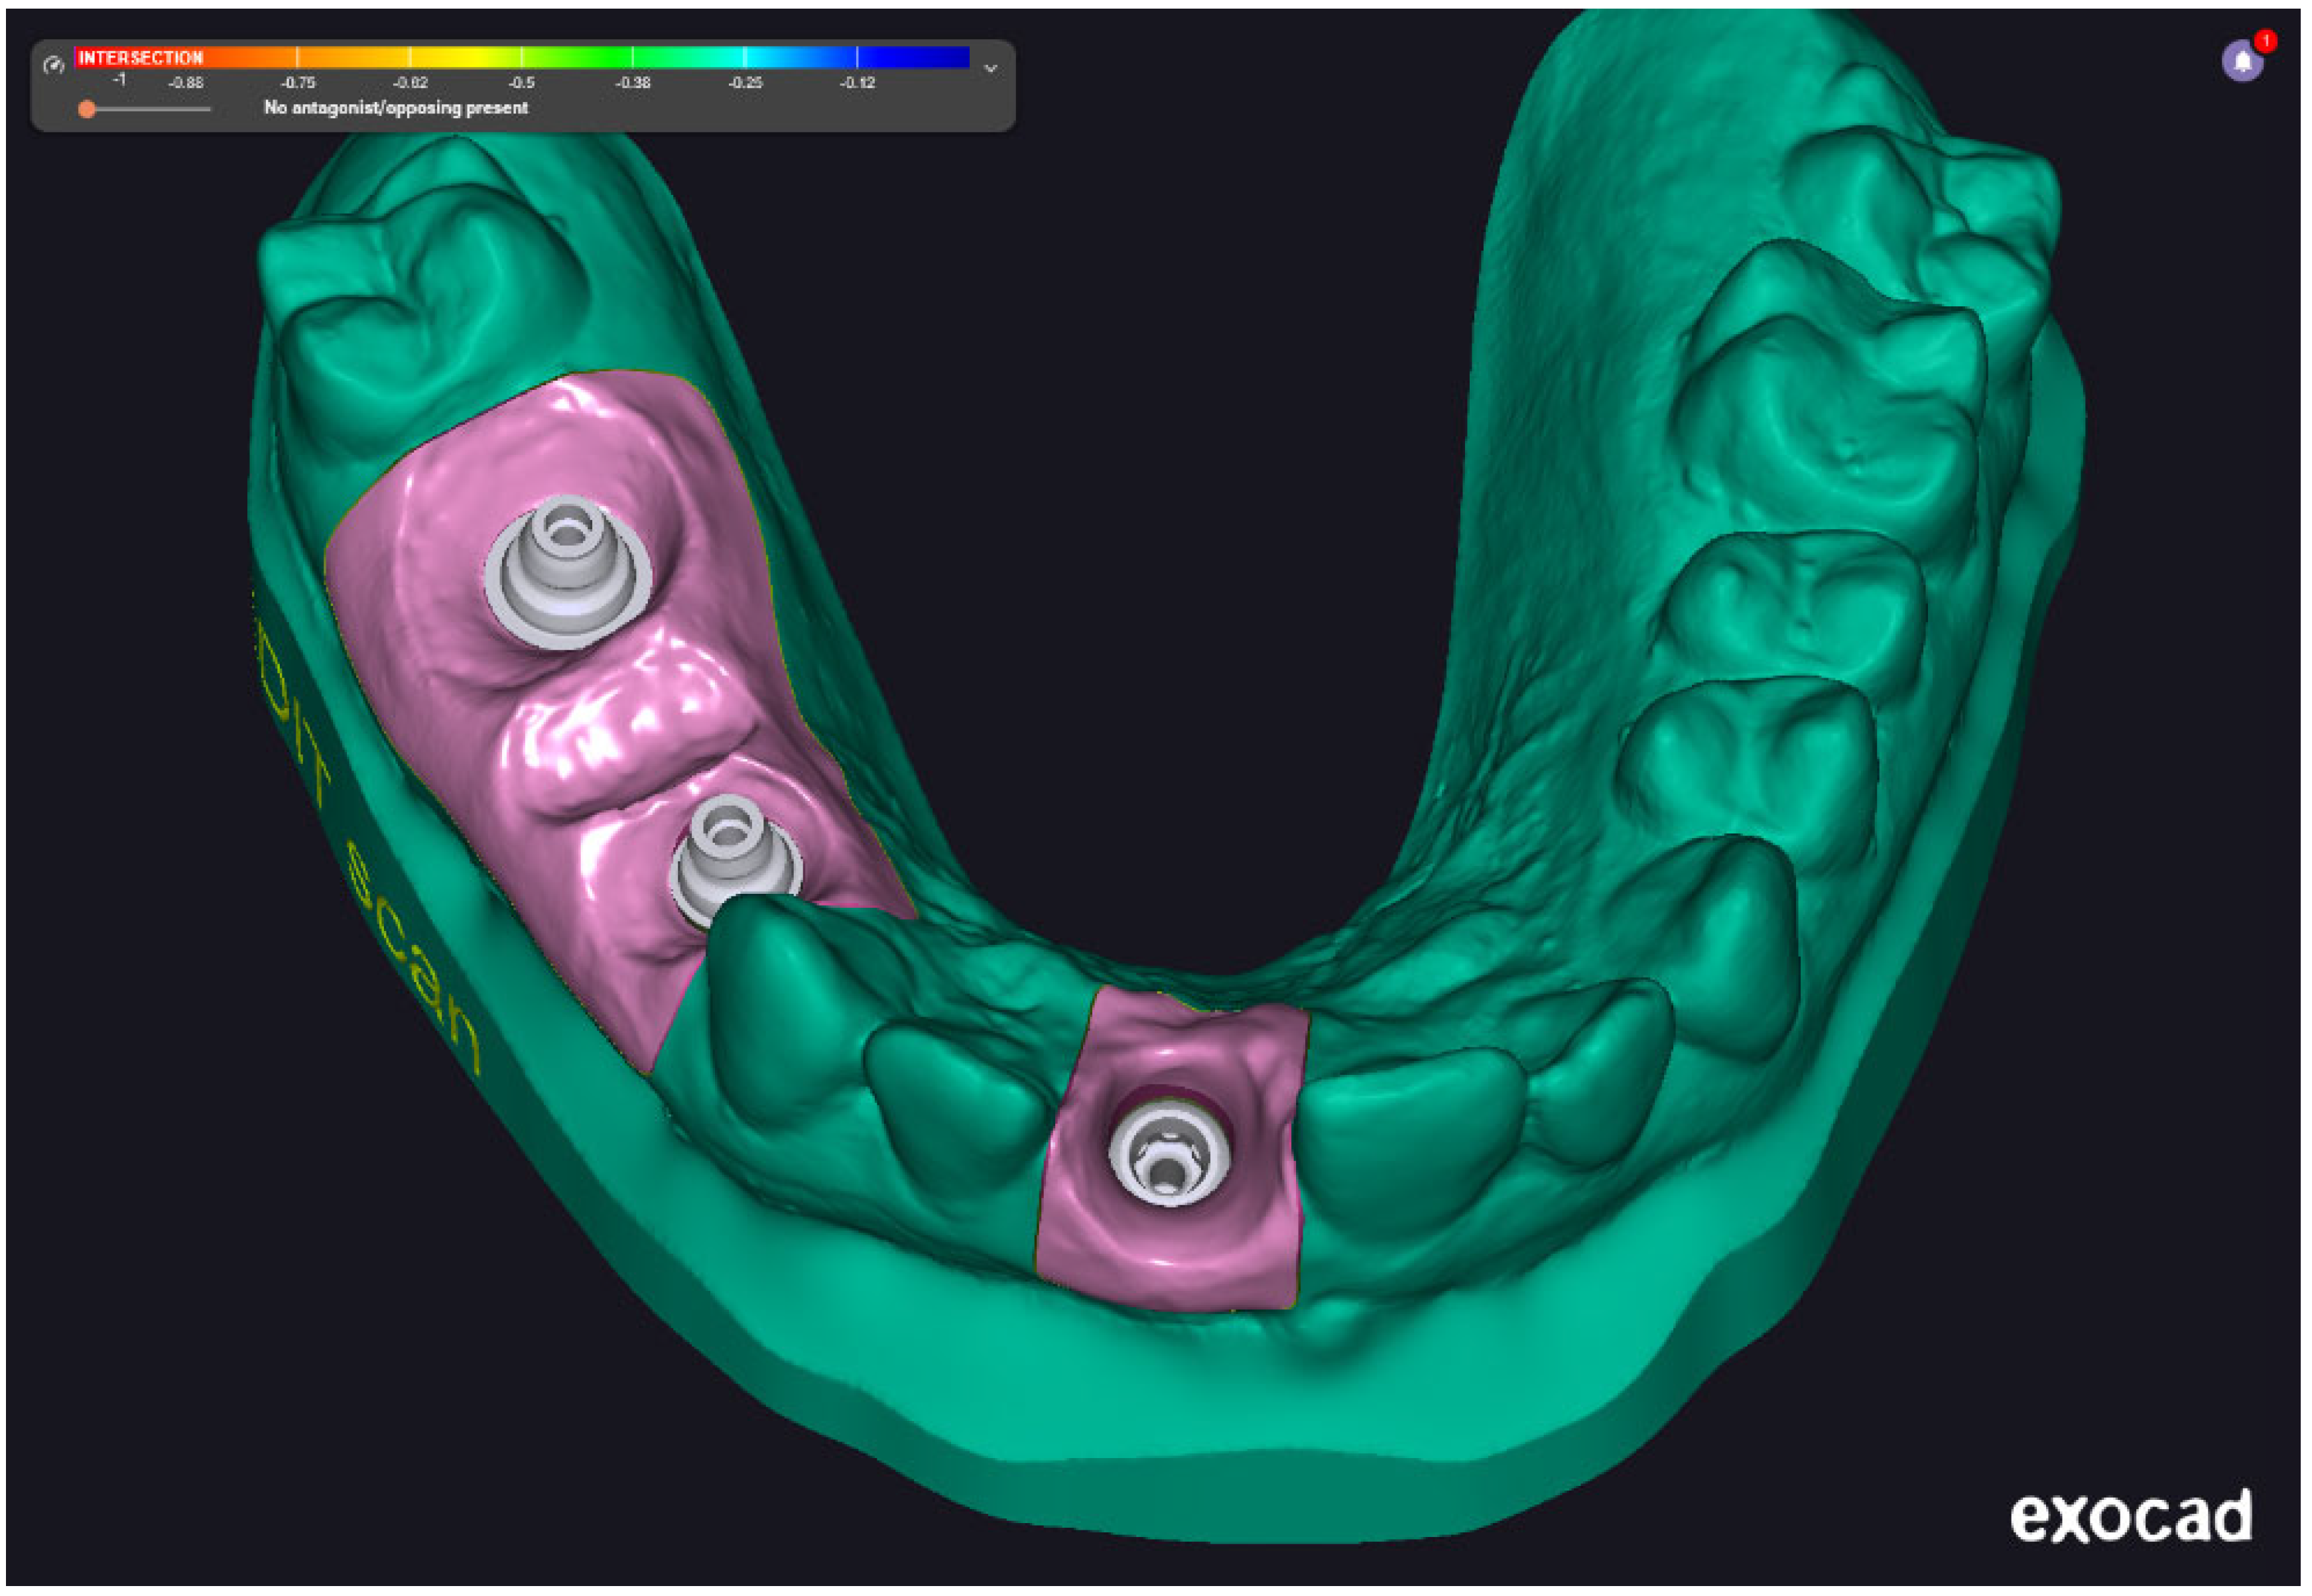

Two intraoral scanners were employed in this study to capture digital impressions: the Medit i700 (Medit Corp., Seoul, Republic of Korea) and the 3Shape TRIOS 3 (3Shape A/S, Copenhagen, Denmark). Both devices offer high-resolution image acquisition and have been validated for use in implant prosthodontics. The digital impression data were saved in STL file format and subsequently processed using Exocad 3.2 Elefsina 9036 DentalCAD software (Exocad GmbH, Darmstadt, Germany). This software facilitated the generation of virtual models, digital framework design, and CAD/CAM workflow integration. Final models and restorations were fabricated via additive and subtractive manufacturing using high-resolution 3D printing and milling systems. Two examples were presented in Figure 3. The examples are not from our cases; it is just illustrative, to present the digital impressions.

Figure 4 shows a finalized digital model made with the help of an impression acquired using Medit i700 intraoral scanner. The scan captures three implant scan bodies and surrounding soft tissue contours within the mandibular arch. The color-coded gingiva mask (highlighted in pink) represents the digitally defined emergence profile and anatomical boundaries of the peri-implant region. This digital model serves as the foundation for virtual prosthetic design and framework planning, enabling precise evaluation of implant angulation, spatial constraints, and occlusal integration prior to CAD/CAM fabrication.

Figure 3. Intraoral scans with (a)—3Shape intraoral scan, (b)—Medit intraoral scan. These images represent illustrative print screens from laboratory software and are not clinical cases included in the study.

Prosthesis 07 00135 g003aProsthesis 07 00135 g003b

Figure 4. Exocad screenshots with the digital model prepared with the impression acquired with Medit intraoral scanner.

Prosthesis 07 00135 g004